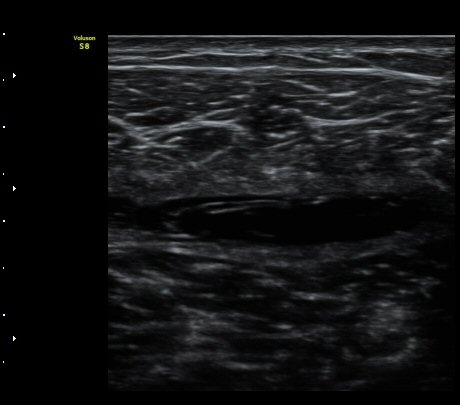

ÃÊÀ½ÆÄ °Ë»ç

¼ö»ó ÈÄ 2ÀÏ Â°

³»Ãø ºñº¹±Ù Á¾´Ü¸é°Ë»ç¿¡¼­ ±ÙÀ°°ú ÈûÁÙ ÀÌÇà ºÎÀ§¿¡ ÀÛÀº ÆÄ¿­°ú ¼ö¾× Àú·ù, ÆÄ¿­ µÈ

±ÙÀ°ÀÇ ±ÙÀ§ºÎ·Î ´ç°ÜÁüÀÌ °üÂû µÊ(±×¸² 1, 2, 3).